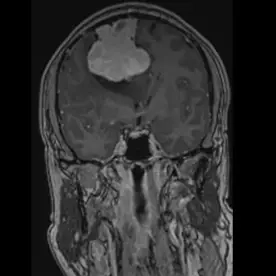

Es zeigt sich eine ausgedehnte Raumforderung des Kleinhirnbrückenwinkels rechts mit einem sogenannten "dural tail sign" (Bild 10-1, Pfeil). Die Raumforderung zeigt ein Wachstum nach intrameatal rechts (Bild 10-2, Pfeil) und entlang des Foramen ovale (Bild 10-3, Pfeil). Es zeigt sich ein ausgeprägtes verdrängendes Wachstum ohne Perifokalödem (Bild 10-4). Insgesamt passt dieses Bild zu einem Meningiom.

Typisches Bild eines Meningioms

- „Dural tail sign“ ist in 60-72 % zu sehen (cave: ein dural tail sign kann auch bei anderen Pathologien vorkommen!)